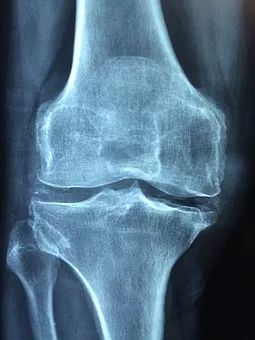

△ 左侧:健康的膝关节,右侧:存在软骨磨损、骨刺、关节退行性变的膝关节

“骨刺”也叫骨质增生,而在医学中其真正的术语是“骨疣”,这是关节因种种原因造成软骨的磨损、破坏,并促成骨头本身的修补、硬化与增生。

疼痛、麻木、红肿、运动障碍等症状,多是增生的骨质比较大,并且累及了神经和血管以及骨质增生造成了局部组织无菌性炎症。

以膝关节骨刺为例,很多中老年人对骨刺认识不足,认为骨刺越磨越好。但实际上恰恰相反,骨刺作为保护性的代偿机制,越磨反而病情越重,严重者甚至需要关节置换。